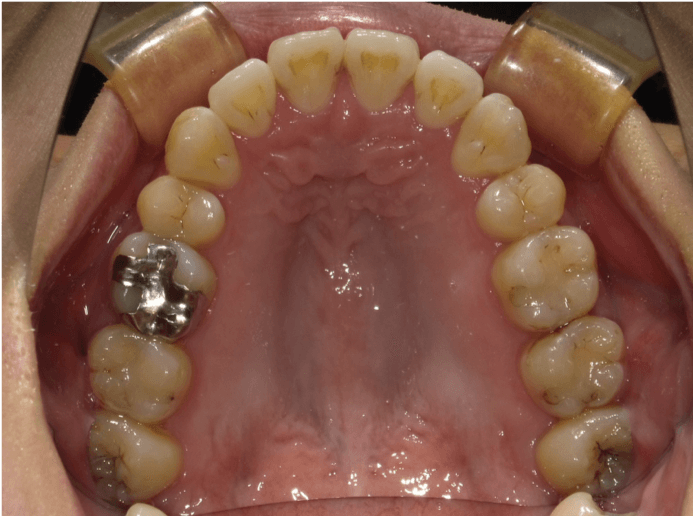

叢生(軽度)

BEFORE

AFTER

担当医コメント

上下に軽度の叢生がある。IPRと歯列の拡大で改善可能と考えインビザラインで治療を行うことにしました。

IPRは被せ物や銀歯の部位に集中させて、歯にかかる負担をなるべく少なくなるように計画した

治療の概要

年齢/性別

26歳 女性

主訴

上下の歯並びが気になる

リスク

歯肉退縮が起こる可能性がある。

費用

82万円(矯正費用)

期間

1 5 ヶ月

術前

術中

術後